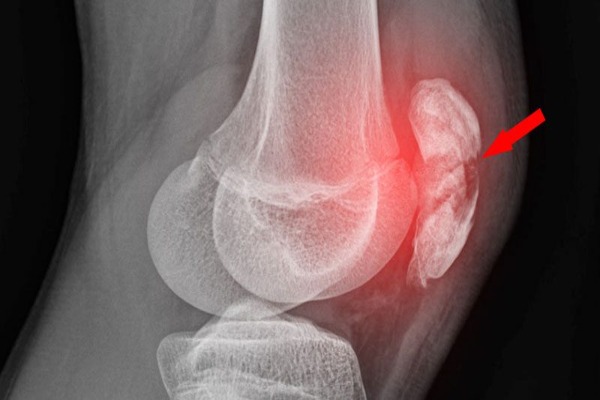

Diz Kapağı Çıkması Nedir, Neden Olur, Nasıl Tedavi Edilir?

Diz Kapağı Çıkması Nedir, Neden Olur, Nasıl Tedavi Edilir? Diz kapağı çıkması, hem sporcuların hem de günlük yaşamda aktif olan kişilerin karşılaşabileceği ciddi bir ortoped

Devamı